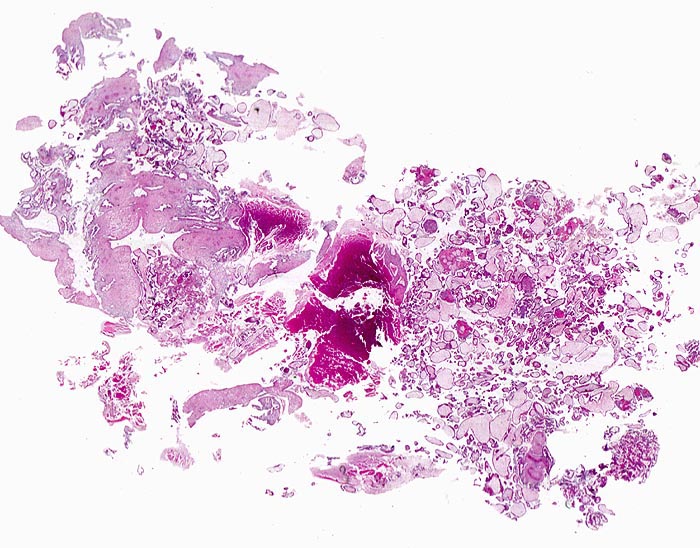

Makroskopie

Befund

Pathologischer Befund

Normalbefund